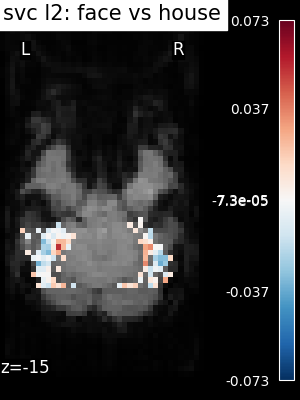

The corresponding weight maps (below) differ widely from one estimator to the other, although the prediction scores are fairly similar. In other terms, a well-performing estimator in terms of prediction error gives us little guarantee on the brain maps.

../_images/sphx_glr_plot_haxby_different_estimators_006.png ../_images/sphx_glr_plot_haxby_different_estimators_005.png ../_images/sphx_glr_plot_haxby_different_estimators_004.png ../_images/sphx_glr_plot_haxby_different_estimators_002.png ../_images/sphx_glr_plot_haxby_different_estimators_003.png